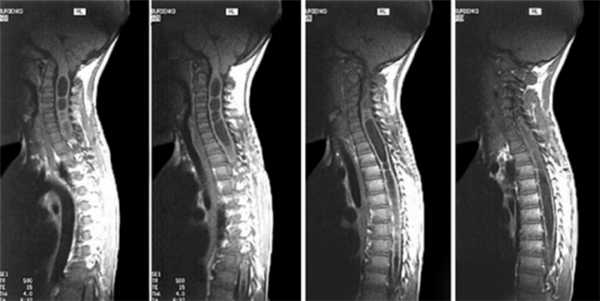

| МРТ опухоль позвоночника | МРТ опухоль спинного мозга | МРТ киста спинного мозга |

Магнитно-резонансный томограф лучше визуализирует мягкие и мозговые ткани и позволяет дифференцировать здоровую ткань и ткань патологическую. МРТ при опухоли поможет определить место очага, вид злокачественного новообразования и степень инвазии в соседние ткани. Кроме того, при МР-томографии не используются вредные рентгеновские лучи, и потому диагностику можно проводить неограниченное количество раз беременным женщинам и детям.

МРТ при опухолях позвоночника

Методом магнитно-резонансной томографии можно выявить грыжи дисков и дегенеративные заболевания. Показывает ли МРТ опухоль позвоночника? Да, при проведении инструментального обследования доброкачественные и злокачественные новообразования будут хорошо видны на снимках. Есть возможность детального исследования самого позвоночного столба, близлежащих мягких тканей, кровеносных сосудов, суставов, связок, нервных окончаний, спинного мозга. Визуализировать метастазы можно даже при их локализации вне основного очага патологии.

При невозможности проведения биопсии, основным способом диагностики онкологии является МРТ. Поставить неверный диагноз можно только при работе с низкопольным томографом, генерирующим низкочастотное поле (за рак можно принять с кисты, скопления жидкости и крови, нагноения).

Результаты МТР обследования при онкологии позвоночника

Оборудование магнитно-резонансной томографии показывает патологическое перерождение тканей, изменения кровоснабжения исследуемых зон позвоночника, определяет трансформации границ, величины и формы внутренних органов. На послойных снимках видна четкая и детализированная картина онкологии от ранних этапов до метастазирования раковых клеток в соседние ткани и регионарные лимфатические узлы.

МРТ обнаруживает сосудистые опухоли, образования нервных структур (в том числе головного и спинного мозга), мягких тканей, паренхимы внутренних органов. Для повышения информативности и выявления онкологии на начальных стадиях используется контрастное вещество. На изображениях томографа хорошо просматривается малигнизация доброкачественных новообразований.

Метод МРТ - достоверный и информативный. Но на основании его данных окончательный диагноз радиолог не ставит. Цель проведения исследования - рекомендовать дополнительное обследование и обнаружить косвенные признаки онкологии.

Отвечая на вопрос, видна ли на МРТ опухоль позвоночника, нужно отметить, что именно этот метод с максимальной эффективностью показывает новообразования спинномозгового канала и спинного мозга.

- Есть возможность точной оценки состояния ликвара, спинного мозга, мягких тканей, сопутствующей дегенеративно-дистрофичной деформации межпозвоночных дисков. Крайне эффективно выявляет опухоль позвоночника грудного отдела МРТ.